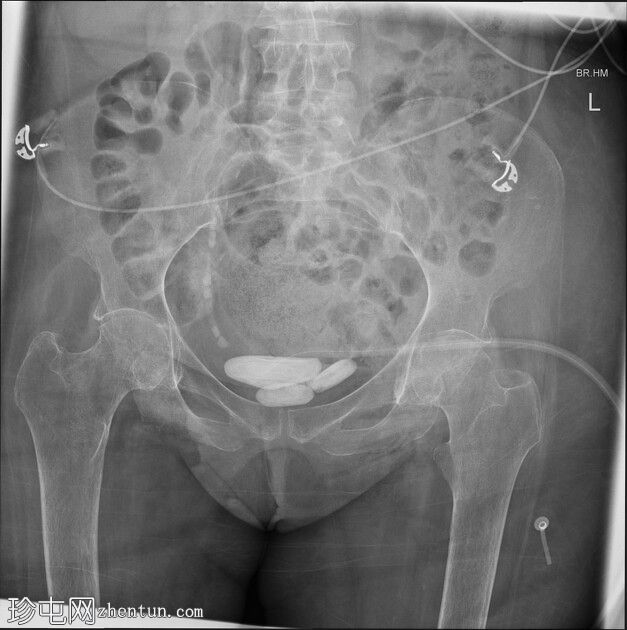

双髋关节居中良好。未见骨折。

右侧坐骨结节骨皮质模糊,与已知的臀部受压区及相关骨髓炎相符。

下盆腔中央可见三处较大的层状钙化影。其中最大的一处直径达6.6厘米,符合膀胱结石的特征。耻骨上膀胱导尿管留置。右侧输尿管下段可见多发小结石(输尿管结石)。右肾部分显影,可见肾结石。

患者既往有因永久性耻骨上膀胱造瘘术(SPC)导致的长期膀胱结石病史。